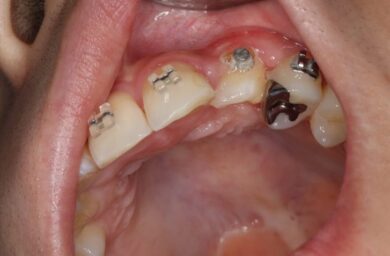

①乳歯を抜歯して、②永久歯にブラケットを装着し、③両側の歯のブラケットと繋げて牽引していきます。

その後ワイヤー矯正治療を行いました。

歯の方向を整えることで、見た目の改善はもちろん、しっかりと咬めるようになります。